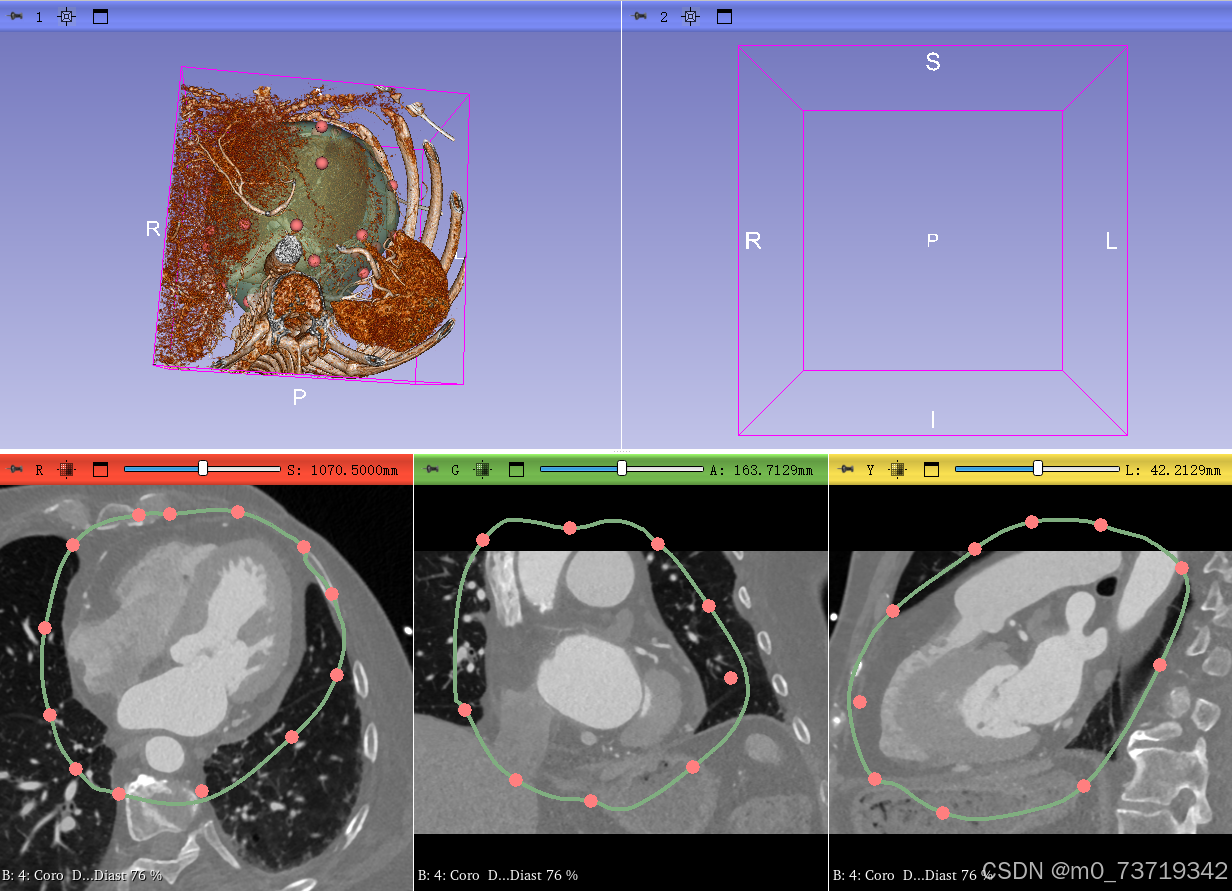

在三个视图中分别圈出心包的位置(注意多圈一些以免血管可能漏,鼠标右键退出圈点功能)如下图所示,可以在三维视图中对圈的范围进行调整

圈完后点击apply完成三维心包分割